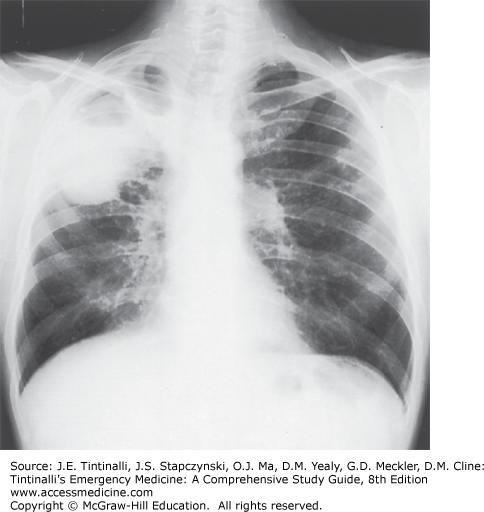

Cavitary tuberculosis of the right upper lobe.